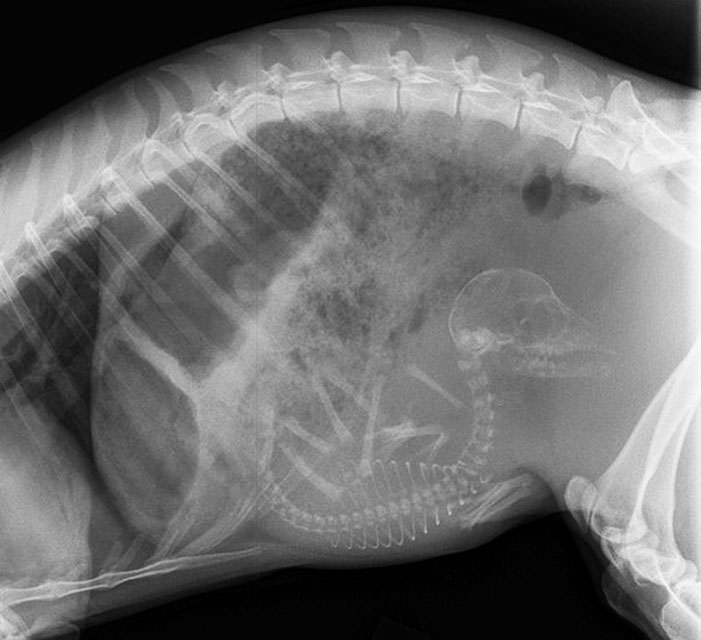

İnsanların ultrason görüntülerini görmeye hepimiz alışkınız. Ancak hamile hayvanların ultrason görüntüleri sizleri çok şaşırtacak.Kaplumbağa

İnsanların ultrason görüntülerini görmeye hepimiz alışkınız. Ancak hamile hayvanların ultrason görüntüleri sizleri çok şaşırtacak.